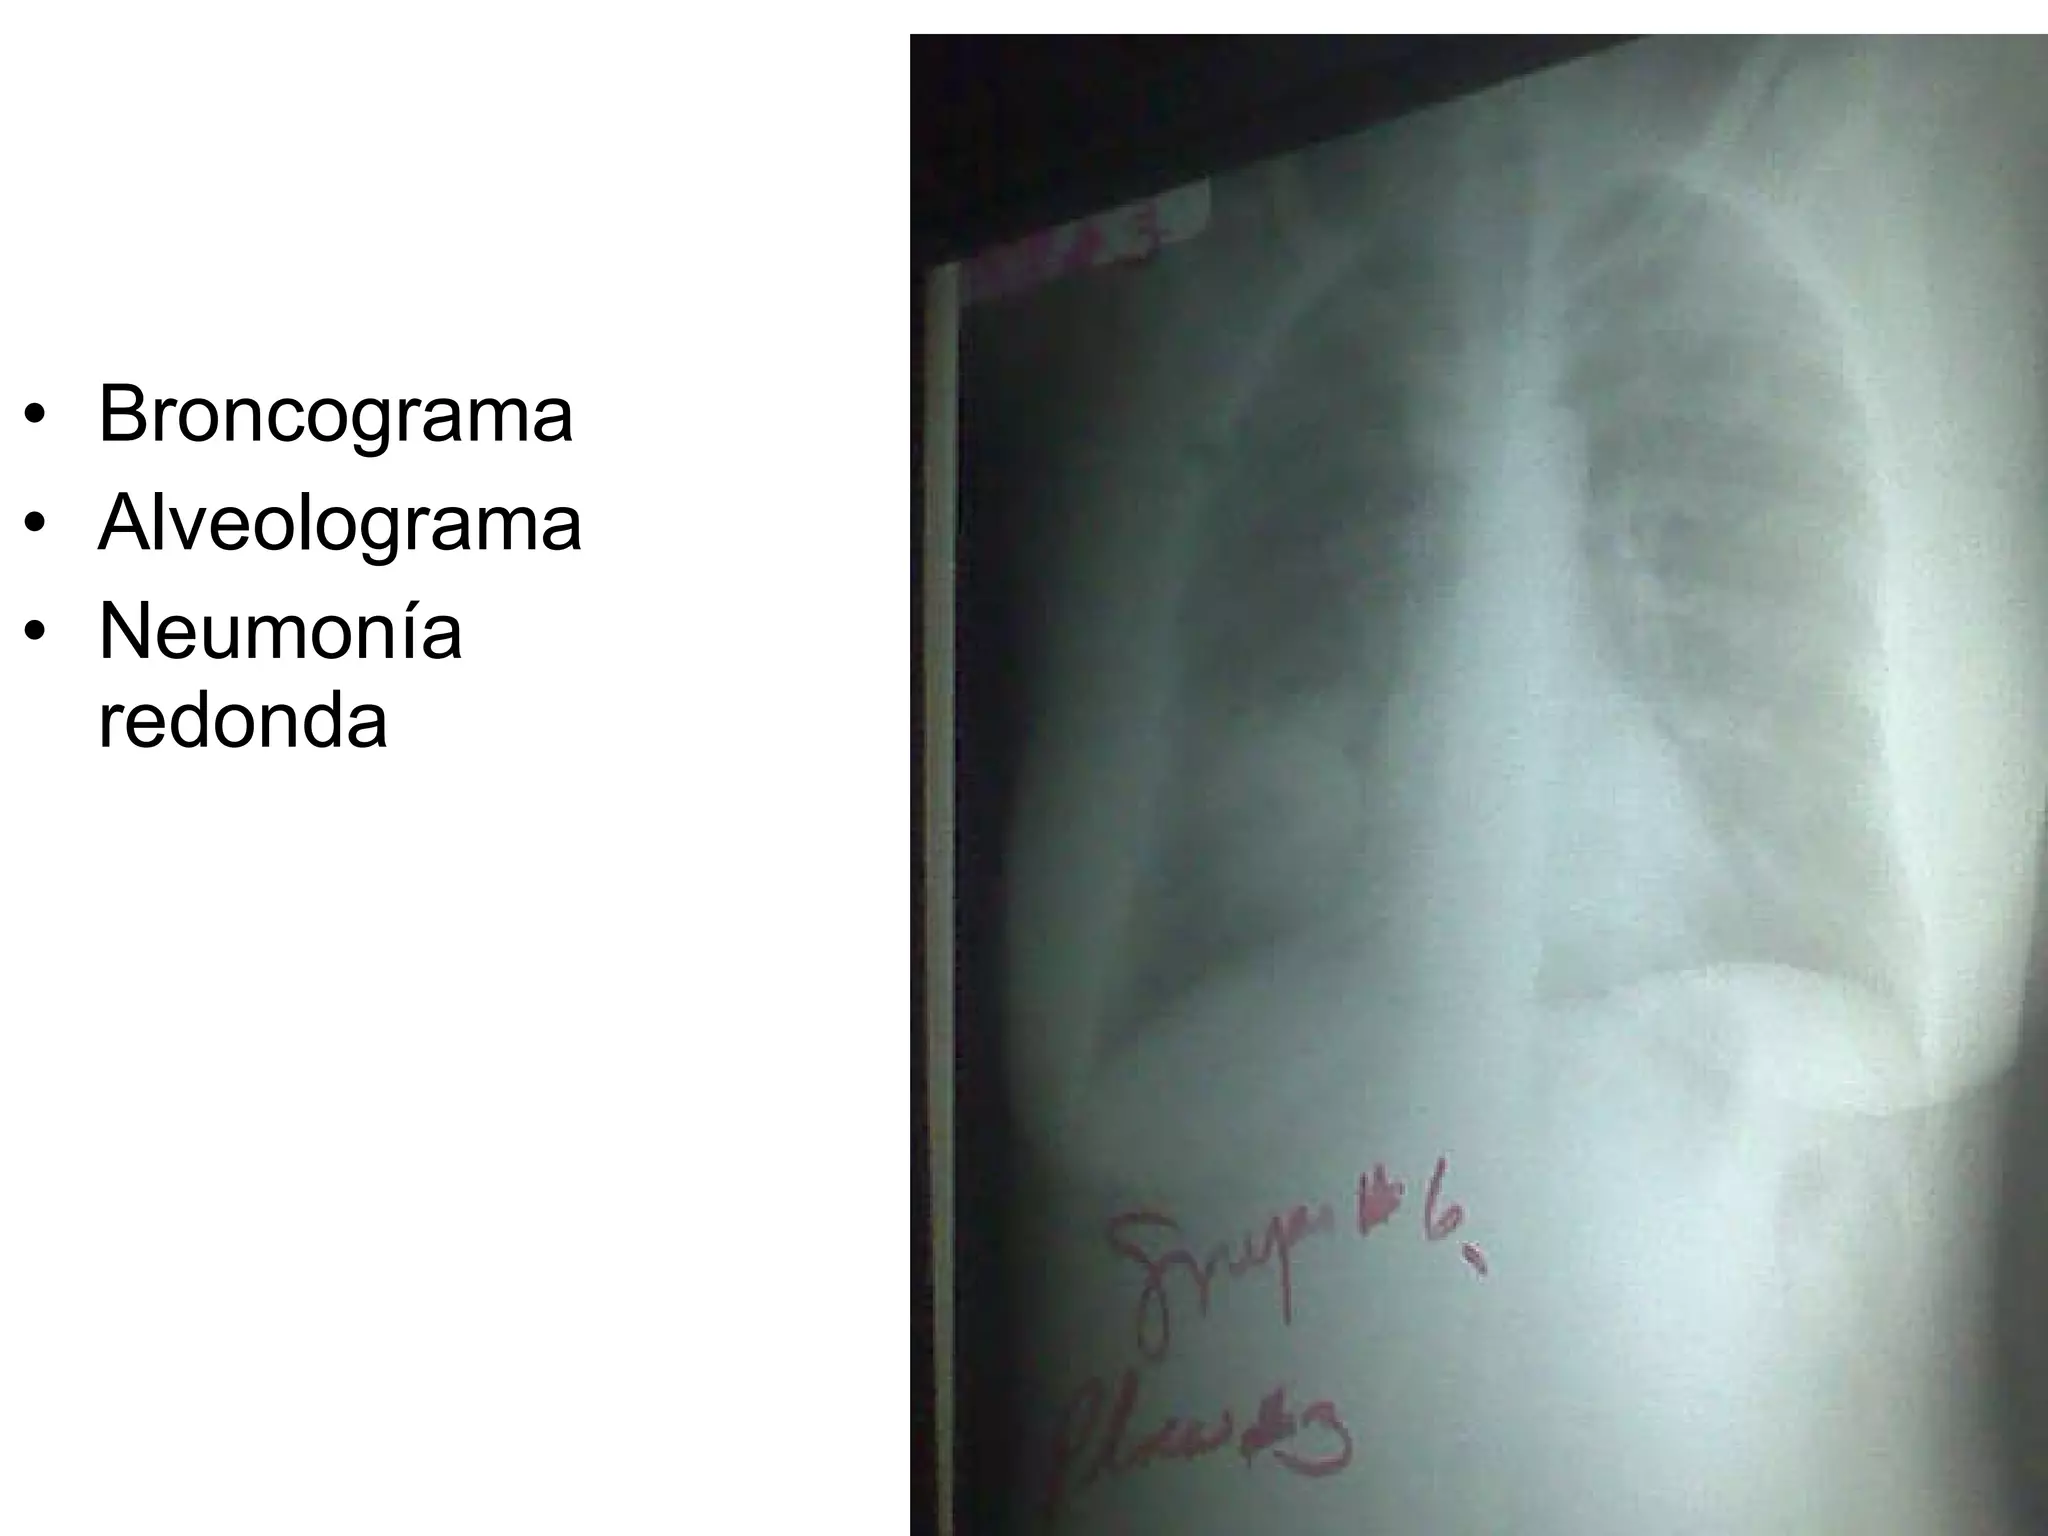

Broncograma Alveolograma Neumonía redonda